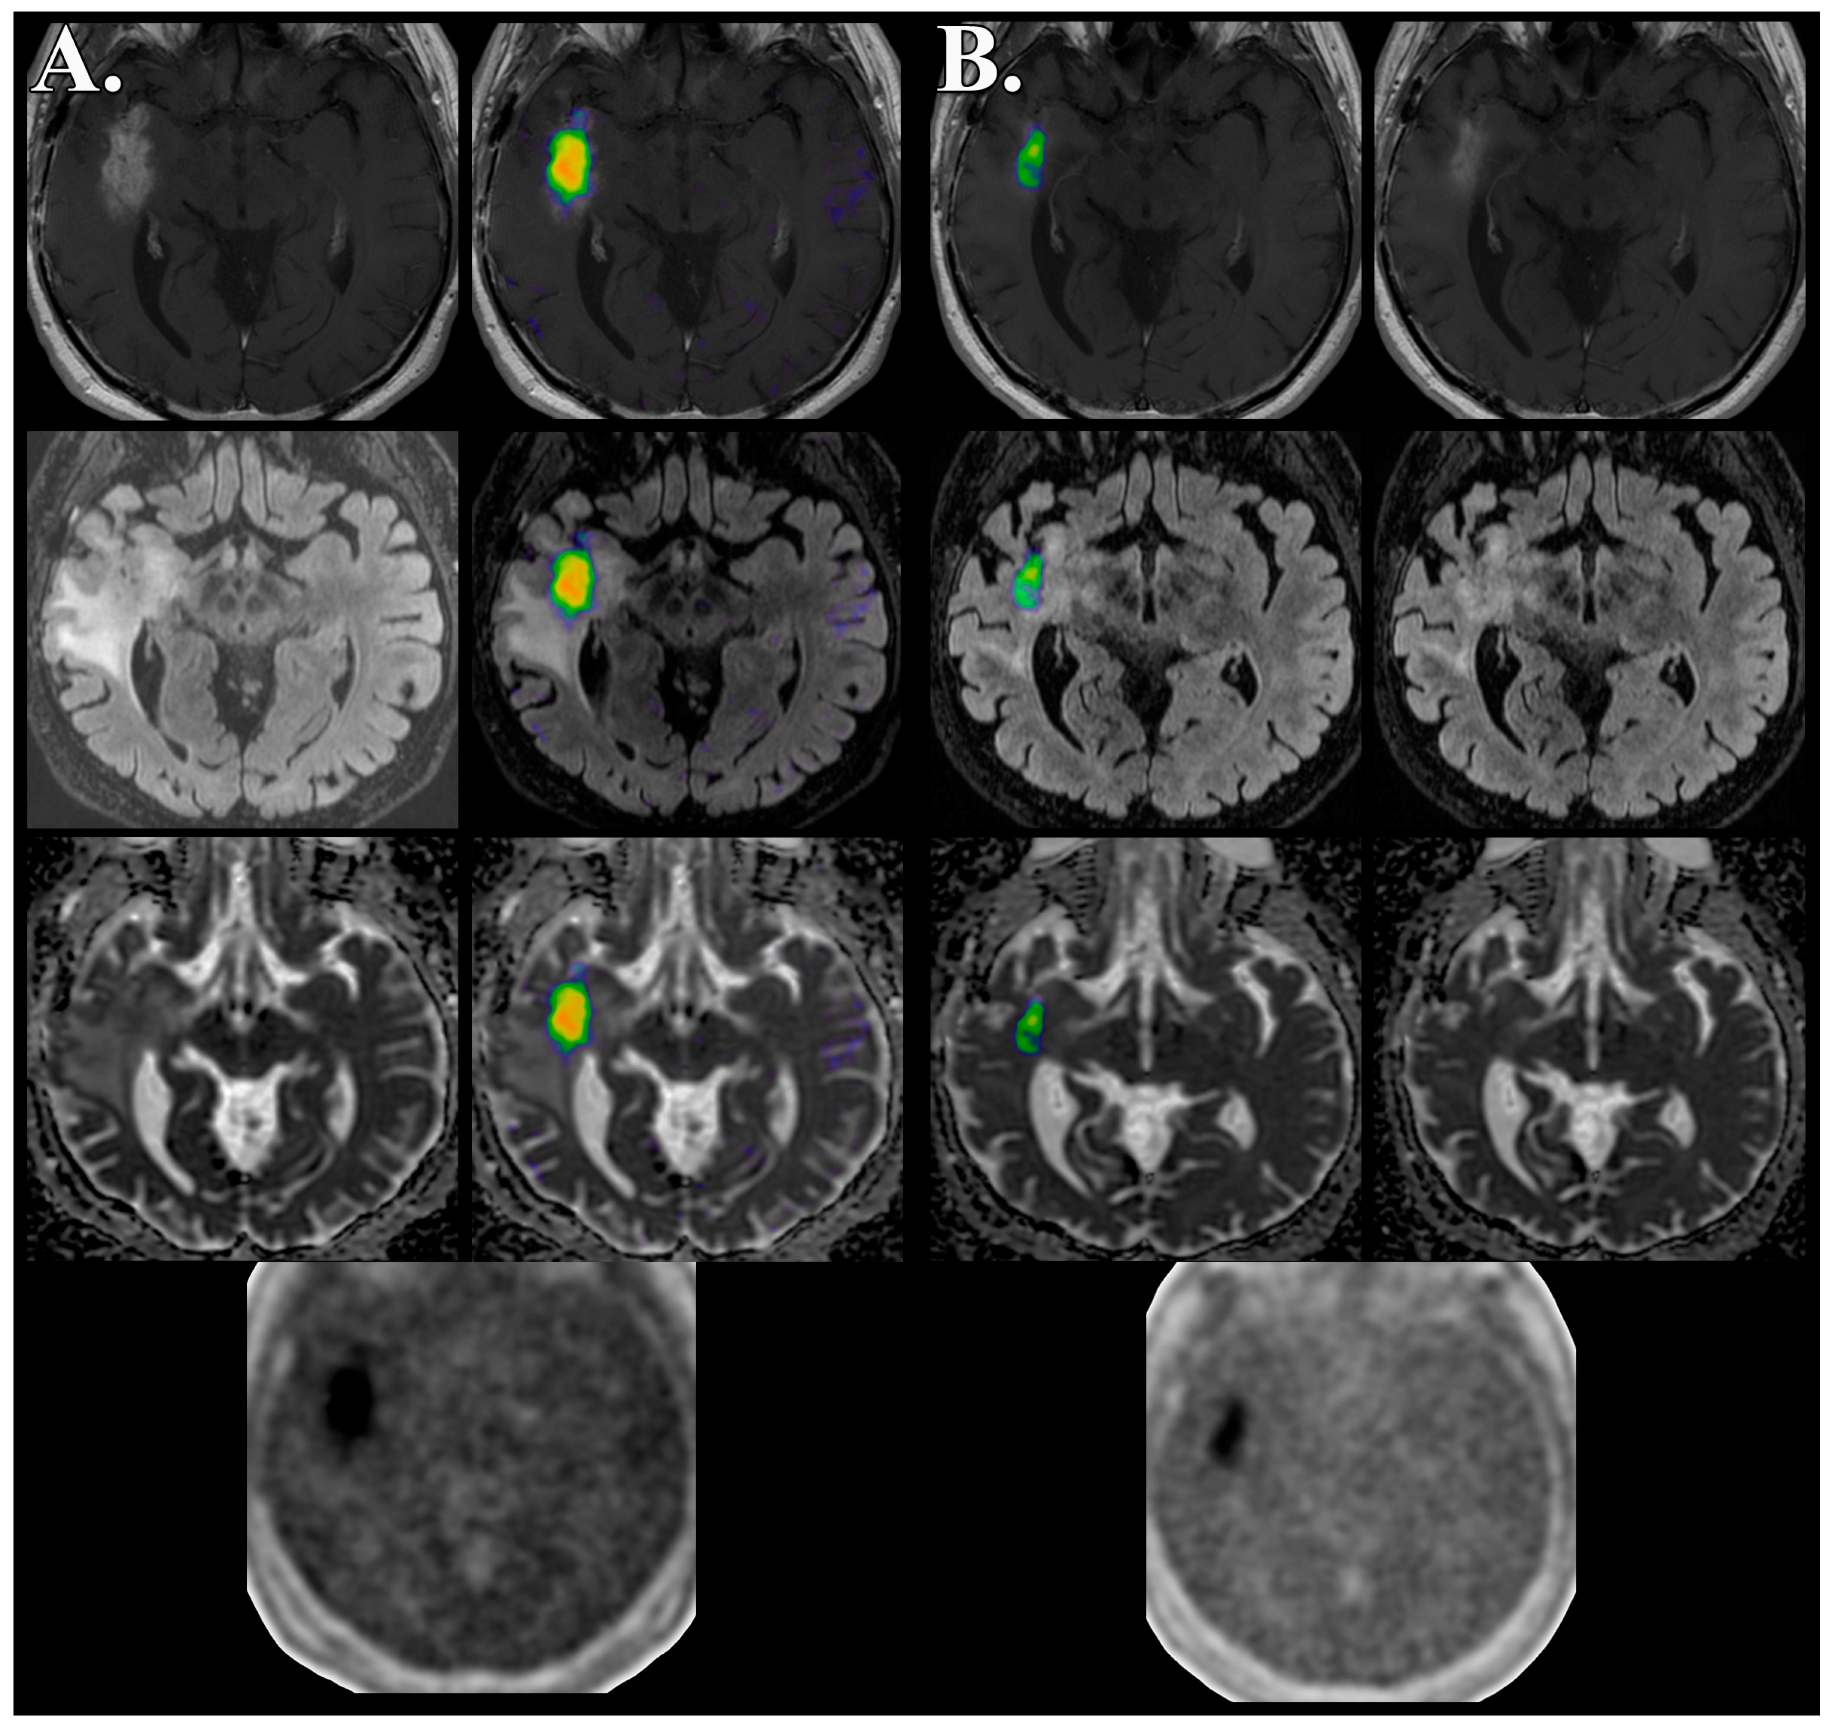

- Barajas, R.F., Jr.; Pampaloni, M.H.; Clarke, J.L.; Seo, Y.; Savic, D.; Hawkins, R.A.; Behr, S.C.; Chang, S.M.; Berger, M.; Dillon, W.P.; et al. Assessing Biological Response to Bevacizumab Using 18F-Fluoromisonidazole PET/MR Imaging in a Patient with Recurrent Anaplastic Astrocytoma. Case Rep. Radiol. 2015, 2015, 731361. [Google Scholar] [CrossRef] [PubMed]

- Barajas, R.F., Jr.; Butowski, N.A.; Phillips, J.J.; Aghi, M.K.; Berger, M.S.; Chang, S.M.; Cha, S. The Development of Reduced Diffusion Following Bevacizumab Therapy Identifies Regions of Recurrent Disease in Patients with High-grade Glioma. Acad. Radiol. 2016. [Google Scholar] [CrossRef] [PubMed]

- Barajas, R.F., Jr.; Phillips, J.J.; Parvataneni, R.; Molinaro, A.; Essock-Burns, E.; Bourne, G.; Parsa, A.T.; Aghi, M.K.; McDermott, M.W.; Berger, M.S.; et al. Regional variation in histopathologic features of tumor specimens from treatment-naive glioblastoma correlates with anatomic and physiologic MR Imaging. Neuro Oncol. 2012, 14, 942–954. [Google Scholar] [CrossRef] [PubMed]

- Barajas, R.F., Jr.; Hodgson, J.G.; Chang, J.S.; Vandenberg, S.R.; Yeh, R.F.; Parsa, A.T.; McDermott, M.W.; Berger, M.S.; Dillon, W.P.; Cha, S. Glioblastoma multiforme regional genetic and cellular expression patterns: Influence on anatomic and physiologic MR imaging. Radiology 2010, 254, 564–576. [Google Scholar] [CrossRef] [PubMed]